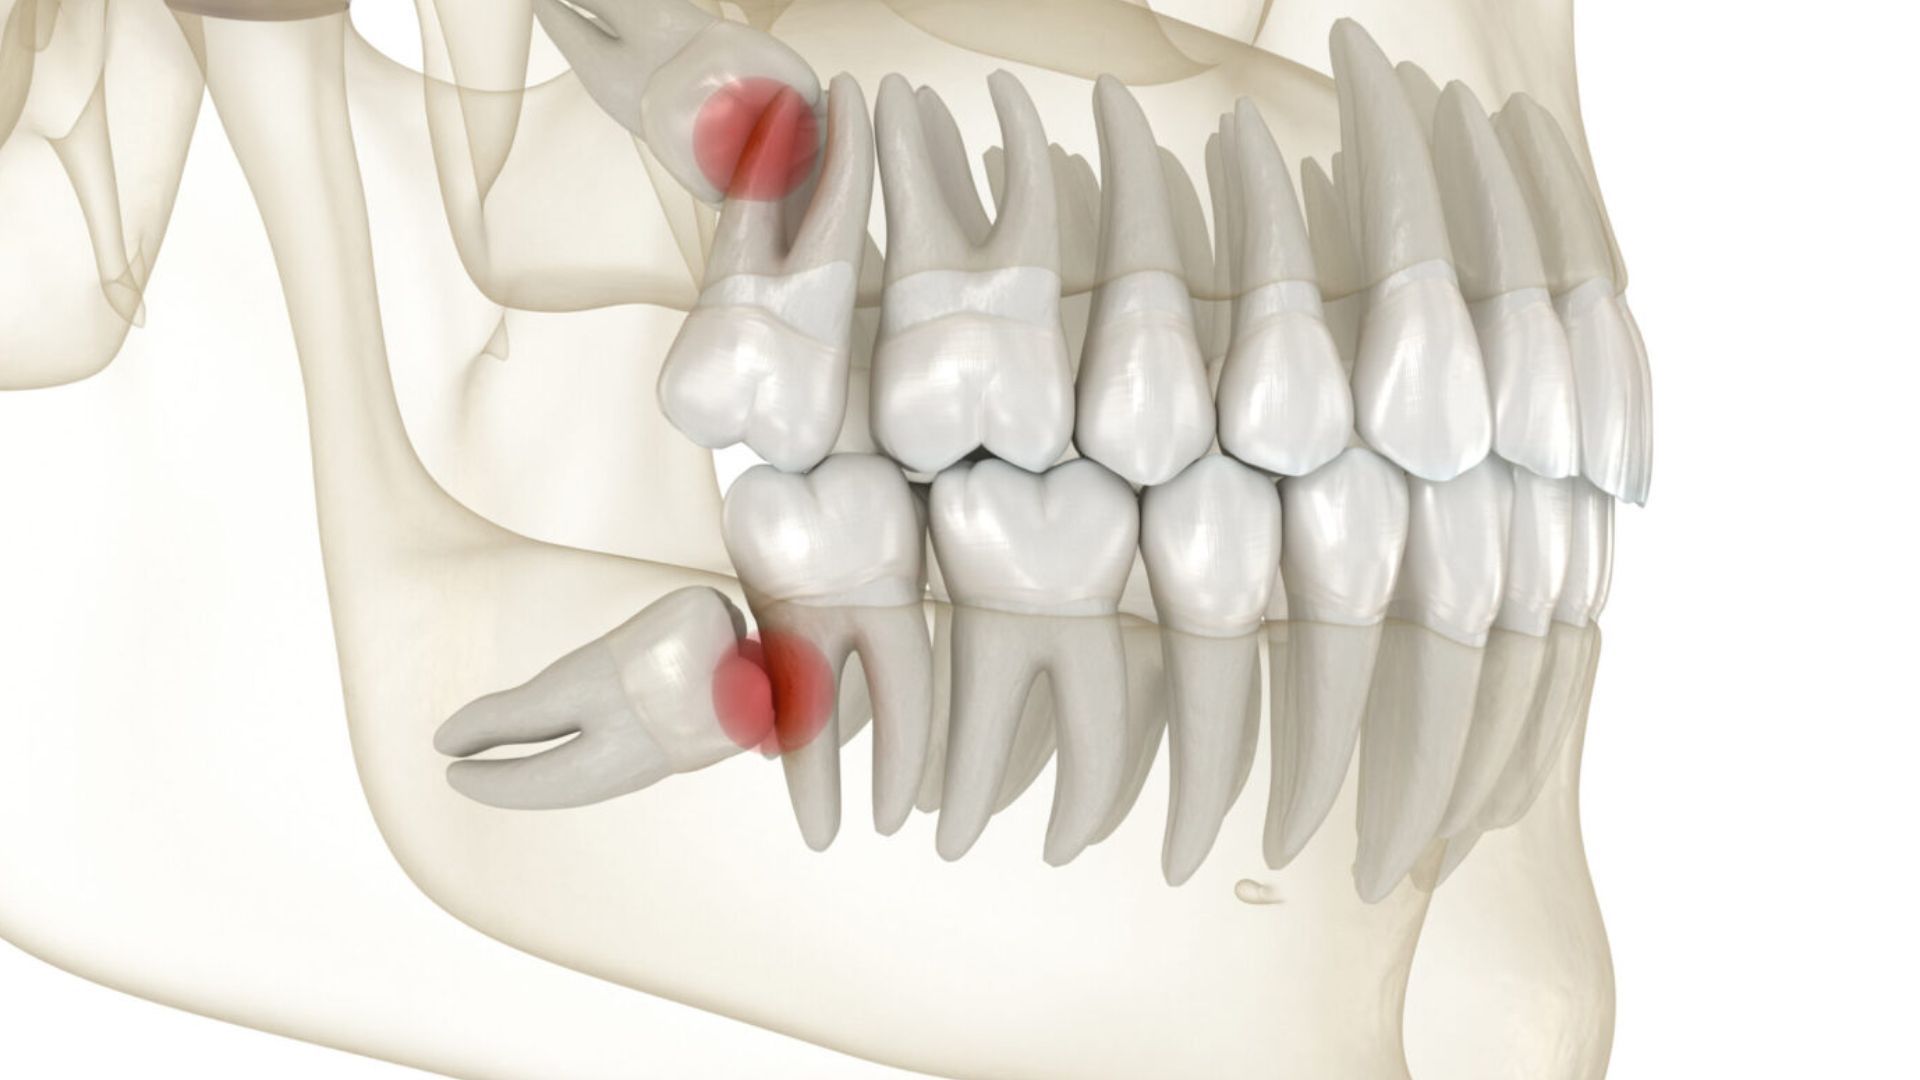

Ngược lại, răng khôn mọc bất thường thường gặp ở đa số trường hợp do hàm hiện đại của con người đã thu nhỏ qua quá trình tiến hóa, không còn đủ chỗ cho răng cuối cùng. Các dạng mọc bất thường phổ biến bao gồm:

- Mọc lệch: Răng nghiêng về phía răng số 7, đẩy hoặc chen lấn răng bên cạnh.

- Mọc ngầm: Răng nằm hoàn toàn trong xương hàm, không trồi lên được.

- Mọc kẹt: Chỉ một phần răng nhú lên, phần còn lại bị nướu che phủ, dễ tích tụ thức ăn.

Tuy nhiên, sự chủ quan với những chiếc răng khôn mọc lệch hoặc mọc ngầm có thể dẫn đến những hệ lụy nghiêm trọng. Vì những biến chứng này thường tiến triển âm thầm và chỉ bùng phát khi đã ở giai đoạn nặng, bạn cần đặc biệt lưu ý các nguy cơ sau:

- Viêm nhiễm tái phát dai dẳng: Do nằm ở vị trí khuất, thức ăn dễ bị mắc kẹt dưới phần nướu che phủ, tạo điều kiện cho vi khuẩn phát triển gây viêm lợi trùm, thậm chí là áp xe (mưng mủ) vùng xương hàm.

- Hiệu ứng domino gây sâu răng: Việc khó vệ sinh khiến răng khôn rất dễ bị sâu. Nguy hiểm hơn, mầm bệnh có thể lây lan sang răng số 7 - chiếc răng đảm nhận chức năng nhai chính làm hỏng cấu trúc của cả hai.

- Hình thành u nang xương hàm: Những chiếc răng mọc ngầm lâu ngày có thể phát triển thành nang chân răng, âm thầm phá hủy cấu trúc xương hàm và ảnh hưởng đến các răng khỏe mạnh xung quanh.

- Tổn thương dây thần kinh: Đối với hàm dưới, răng khôn mọc lệch lạc có thể chèn ép trực tiếp vào ống thần kinh, dẫn đến tình trạng tê bì hoặc mất cảm giác ở vùng môi, cằm và lưỡi.